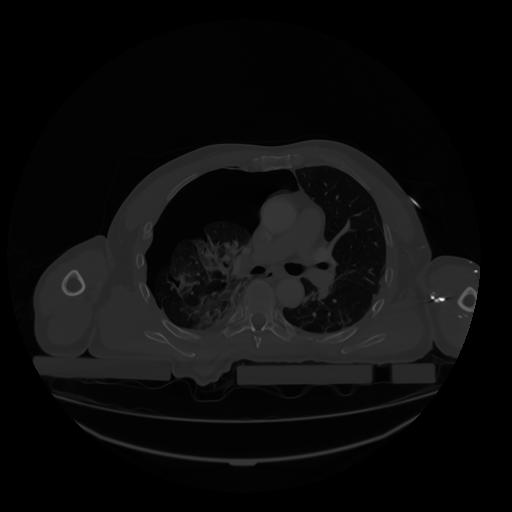

28 CUERPO,CE,Vol,2.0,CUERPO,,